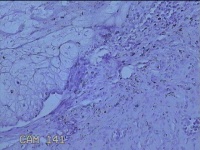

面部、下颌肿物

性别

女

年龄

36岁

临床诊断

皮脂腺囊肿

一般病史

无

标本名称

大体所见

灰白暗红色带皮肤样肿物1.3x0.8x0.3cm一个,表面光滑,起开肿物呈实性,切面灰白暗红色,质软。